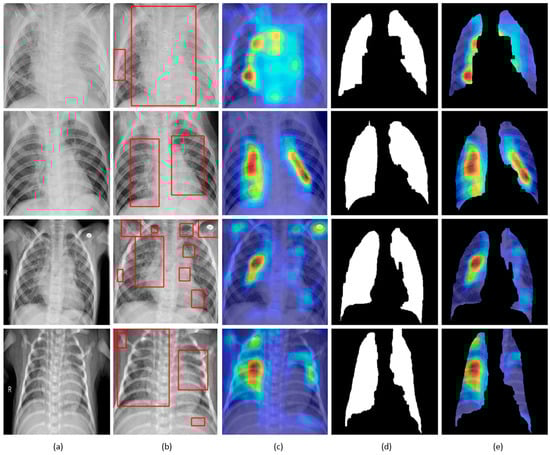

Figure 12.

Visual explanations through gradient-based localization using grad-CAM: (a) Input CXRs; (b) Bounding boxes localizing regions of activations; (c) Grad-CAM showing heat maps superimposed on the original CXRs; (d) Automatically segmented lung masks; (e) Grad-CAM showing heat maps superimposed on the cropped lungs.

CXRs are fed to the trained model and the predictions are decoded. The heat maps are generated as a two-dimensional score grid, computed for each input pixel location. Pixels carrying high importance with respect to the expected class appeared bright red with distinct color transitions for varying ranges. The generated heat maps are superimposed on the original input to localize image-specific ROI. The lung masks that are generated with the boundary detection algorithm are applied to extract the localized ROI relevant to the lung regions. We observed that CAM and grad-CAM visualizations generated heat maps for the pneumonia class to highlight the visual differences in the “pneumonia-like” regions of the image.

We applied our novel method of average-CAM and average-grad-CAM to visualize the class-specific ROI, as shown in Figure 13 and Figure 14. Lung masks are applied to the generated heat maps to localize only the ROI specific to the lung regions. We observed that the class-specific ROI localized by the average-CAM and average-grad-CAM for the viral pneumonia class follows a diffuse pattern. This is obvious for the reason that viral pneumonia manifests with diffuse interstitial patterns in both lungs []. For the bacterial pneumonia class, we observed that the model layers are activated on both sides of the lungs, predominantly on the upper and middle right lung lobes. This is for the reason that bacterial pneumonia manifests as lobar considerations []. The pneumonia dataset under study has more pediatric patients with right lobar consolidations.